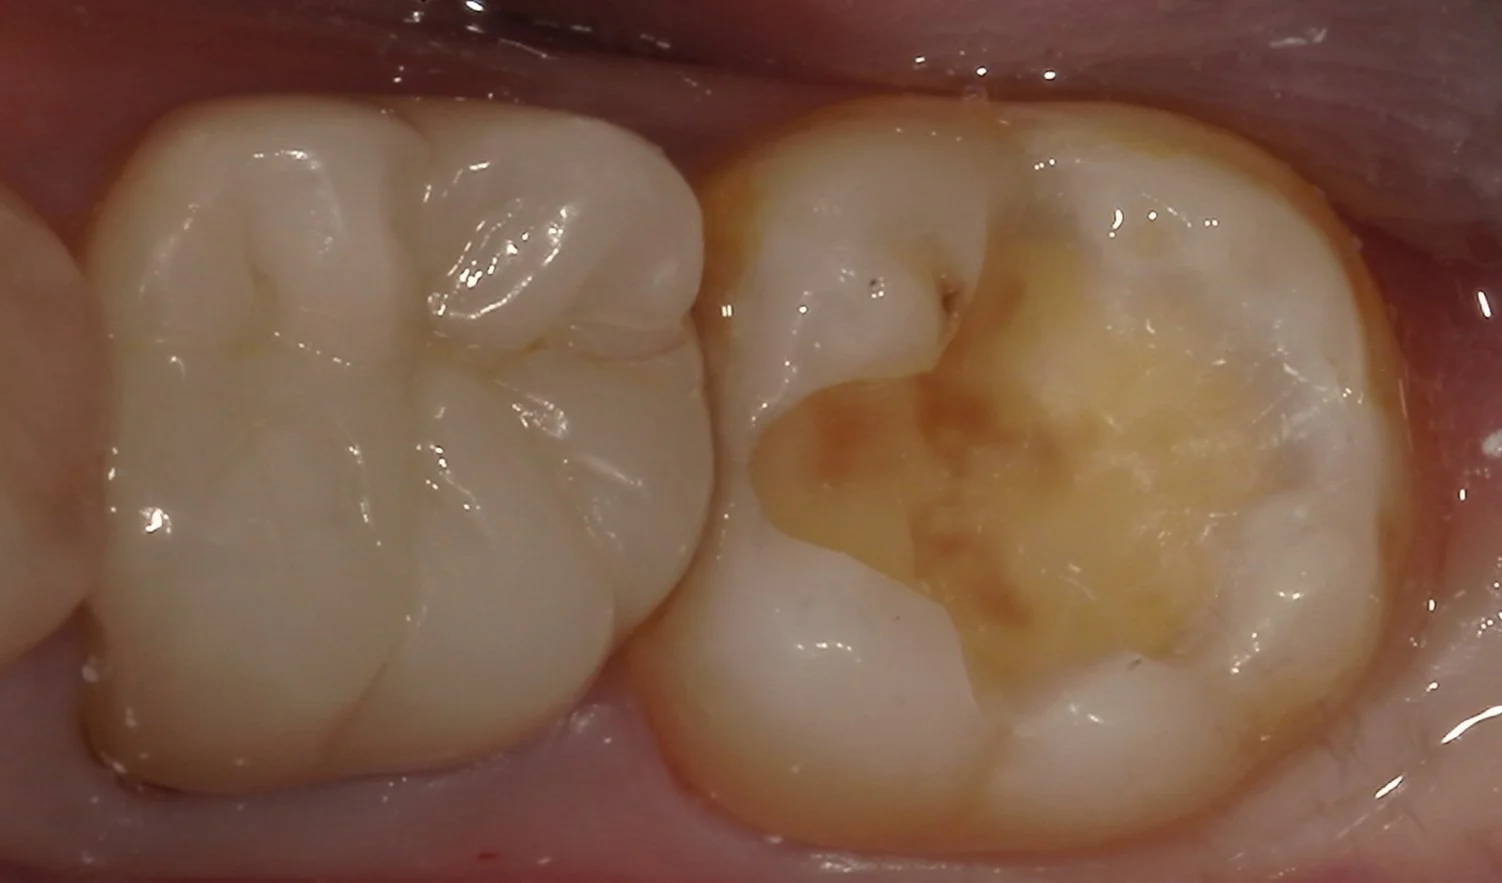

では、実際に詰め物のみを外し、虫歯を見えやすくしたものを見てみましょう。

ご覧の通りです。

前の詰め物を取りきらずに、その部分だけを治療することを補修修復と言いますが、これは何でもかんでもに使える手法ではありません。

特に今回のように内面に虫歯が入り込んでるのが見た目でも分かるようなレベルの場合は、一度詰め物と虫歯を完全に取りきった方が治療の予後は圧倒的に良くなります。

虫歯を取りきるとこんな感じでした。

非常に大きかったので、所々着色が残ってしまっていますが、別に虫歯というわけではありません。

健康な層がしっかりと露出させることが出来たので、そのまま詰めていきます。